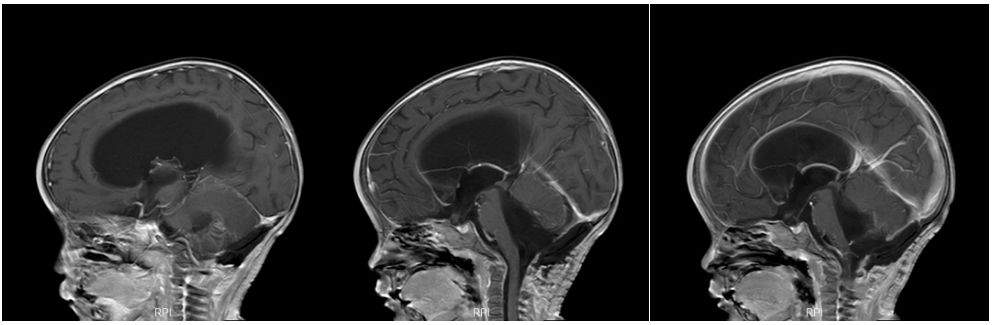

头颅增强磁共振提示:第四脑室区肿瘤,伴幕上脑积水、间质性脑水肿,肿块包绕基底动脉,室管膜瘤首先考虑。

图2. 头颅MR增强:见后颅窝肿块轻度强化,四脑室出口生长进入脑干侧前方,包绕椎动脉、小脑后下动脉等分支,向下延伸进入椎管内。